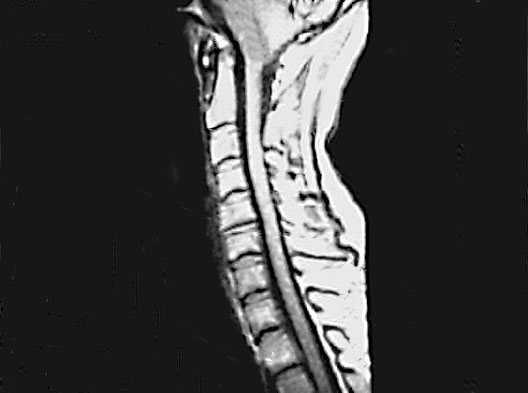

Cervical Spine Zoom

Roll mouse over image to display labels.

1. Body of Second Cervical Vertebra (Axis)

2. Body of Third Cervical Vertebra

3. Subarachnoid Space

4. Intervertebral disc between C5 and C6

5. Body of Second Thoracic Vertebra

6. Medulla Oblongata

7. Spinal Cord

8. Spinous Process of 7th Cervical Vertebra (Vertebra Prominens)